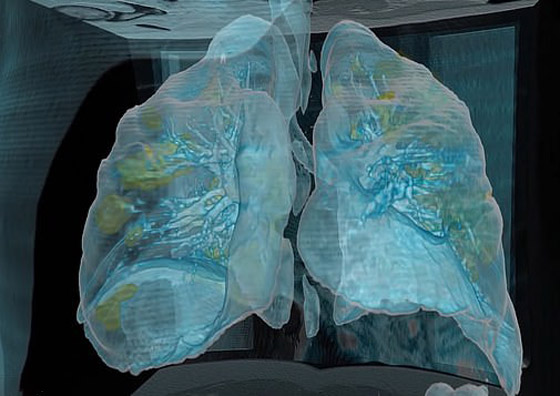

تصوير مقطعي محوسب من مستشفى جامعة جورج واشنطن يُظهر آثار فيروس كورونا المستجد، أو ما يُعرف بـ"كوفيد-19"  رئتي رجل عمره 59 عاماً. فشاهدوا معنا في الفيديو المدهش أدناه كيف تبدو رئة مصاب بفيروس كورونا (فيروس كوفيد 19) وما يحصل داخلها..